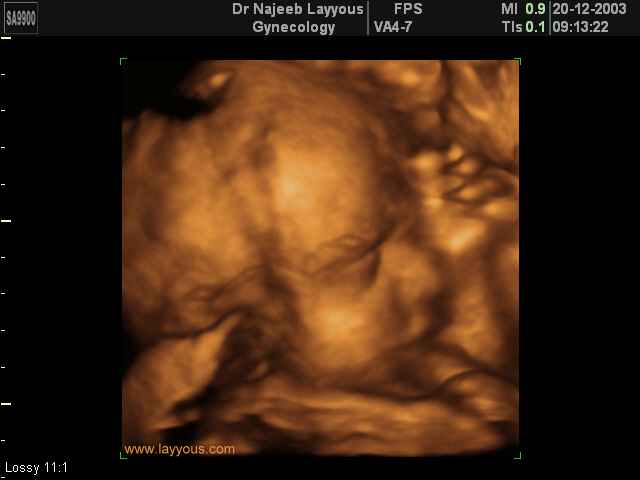

- 3D Fetal Profile Ultrasound Scan Photos

3D Fetal Profile Ultrasound Scan Photos | Dr N Layyous